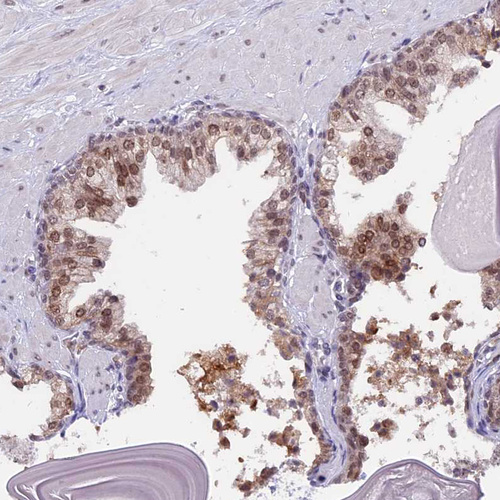

Immunohistochemical staining of human Fallopian tube shows strong nuclear positivity in glandular cells.